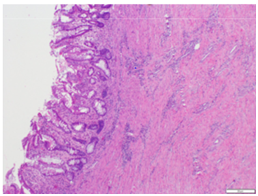

The entire strictured area was submitted for microscopic analysis. These sections showed chronic inflammation, crypt architectural distortion, and marked submucosal fibrosis with a multifocal lymphoplasmacytic infiltrate (Figure 1 & 2). No neoplasm was identified. Immunohistochemical stains for IgG (Figure 3) and IgG4 (Figure 4) were performed that highlighted foci of lymphoplasmacytic aggregates and many IgG4 positive plasma cells within the fibrotic areas. The histologic and immunophenotypic evidence supported the diagnosis of IgG4 related enteropathy in this patient.

Figure 1 Microscopic analysis of strictured area containing Chronic inflammation, Crypt architectural distortion.